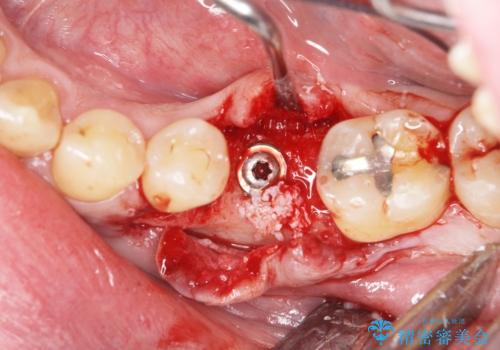

- 奥歯を失ったのち放置してしまった部位にインプラント治療を希望されて来院されました。

少量の骨造成を併用したインプラント治療を計画します。

インプラン治療は、ブリッジと異なり前後の歯を削る必要がなく、入れ歯と違い取り外しの必要がありません。